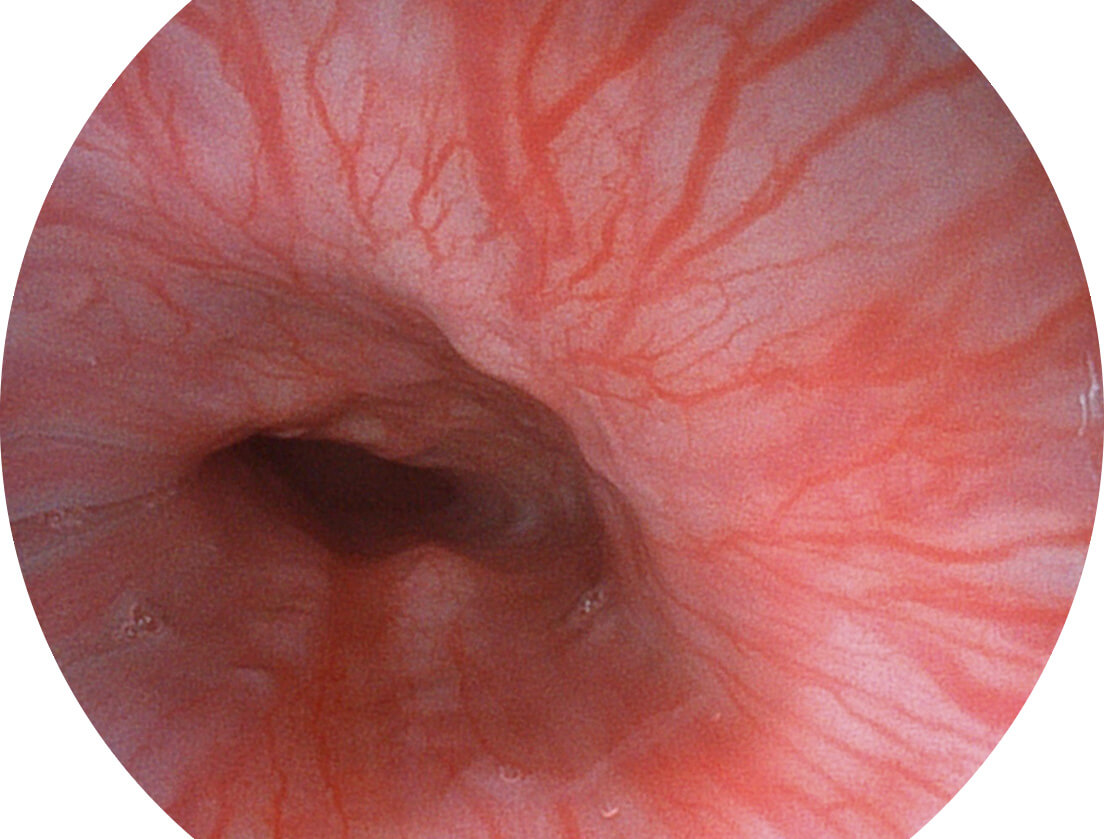

强调浅层黏膜结构的同时,保证照明亮度和提升浅层微血管与中层血管颜色对比度,病变边界更清晰。

• 白光图像 VIST图像